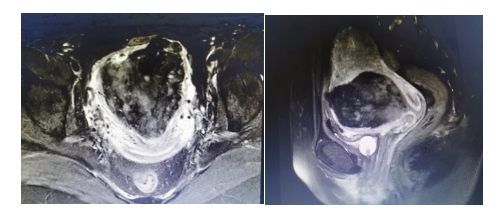

入院后完善相关术前检查,根据患者年龄及生育要求制定个体化的手术方案:1.患者诊断明确,有子宫出血,病灶较大,有手术指征;2.患者年轻,有再生育要求,需保留子宫。根据诊疗指南及患者病情,为减少术中出血量,拟定行双侧髂内动脉暂时阻断及腹腔镜下瘢痕妊娠病灶切除及子宫修补术,术前积极备血。

该患者既往2次剖宫产史,仍有生育需求,且拒绝再次开腹手术。药物流产及清宫手术均失败,病灶较大,有持续性出血,属于重型Ⅲb型子宫瘢痕妊娠,不适宜药物保守治疗。患者子宫动脉介入栓塞术,费用高,且术后对女性生育力有潜在的影响,可能导致卵巢功能下降、宫腔粘连、胎儿宫内生长受限、早产等。对该患者我们结合诊疗指南并巧妙变通,制定了暂时性阻断髂内动脉后再切除病灶并修补子宫的方法,术中明显减少出血,子宫修补成型较高,且微创美观,患者恢复快,满意度高。为重型剖宫产瘢痕妊娠患者提供了更微创有效的治疗方案,更好的保护患者生育力,降低不良结局发生率。